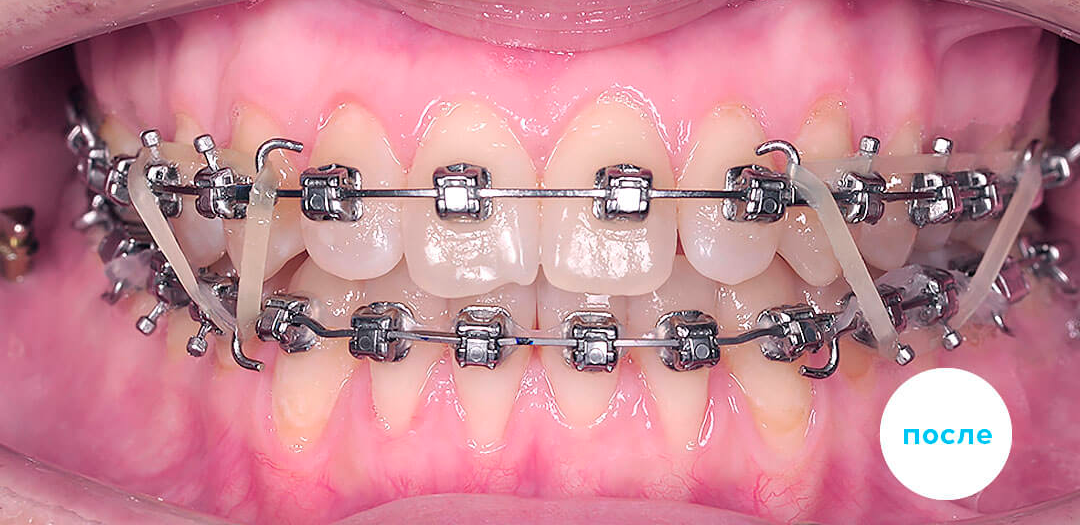

В большинстве случаев показано использование несъемных ортодонтических конструкций – установка брекет-систем (лигатурных или самолигирующихся). Челюстно-лицевые операции рекомендованы для коррекции прикуса в крайнем случае – если аномалию окклюзии не удалось устранить другими методами.

Результаты лечения